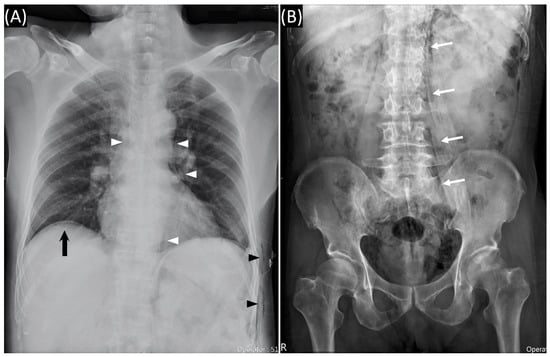

Figure 2. (A) Chest radiography showed subcutaneous emphysema (black arrowheads), pneumomediastinum (white arrowheads), and subdiaphragmatic free air (black arrow). (B) Abdominal radiography showed paraspinal air which outlines the psoas muscle (white arrows).